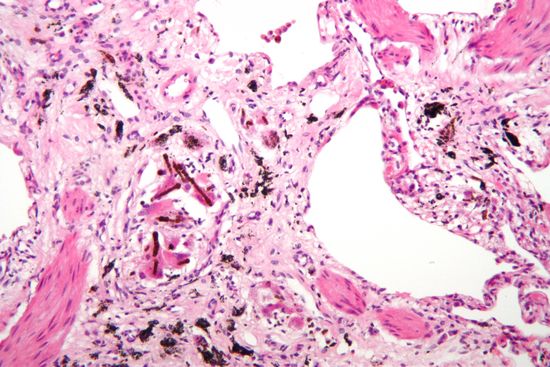

Op deze begraafplaats in Kapelle-op-den-Bos liggen jammer genoeg een groot aantal doden die veroorzaakt werden door asbest. Asbest was via het bedrijf Eternit één van de grootste bronnen van welvaart. Maar ook tevens een sluipende moordenaar. Asbest is al eeuwen bekend. Het werd al vlug onderkend vanwege zijn brandwerende eigenschappen: in het Rome van de oudheid gebruikten de Vestaalse maagden het voor hun lampenpitten voor eeuwig brandende lonten. De Romeinse schrijver Plinius spreekt ook van een onbrandbare stof die gebruikt werd als lijkwaden voor koningen. Hierdoor werd de as van het vuur niet gemengd met de as van de edele. Arabische troepen zouden asbest in de strijdkledij verwerkt hebben zodat ze bij een bestorming brandbommen konden gebruiken en toch zelf aanvallen. Karel de Grote had een tafelkleed van asbest dat hij tot verbijstering van zijn gasten in het vuur wierp na de maaltijd. In de Eerste Wereldoorlog zijn de vezels toegepast als filtermateriaal in gasmaskers. Zolang asbest in gebonden toestand verkeert, is er geen gevaar voor de gezondheid. Als losse asbestvezels worden ingeademd lopen zij vast in de kleine luchtwegen en longblaasjes. Daar worden de kleine vezels opgenomen door opruimcellen. Vezels die hiervoor te groot zijn, kunnen gaan migreren (wandelen) in de weefsels. Ook kunnen zij zich via de lymfebanen verspreiden en zo terechtkomen op plaatsen ver verwijderd van de kleine luchtwegen. Als gevolg van blootstelling aan asbest kunnen verschillende asbestziekten ontstaan zoals asbestose, asbestpleuritis, fibrose, longkanker, mesothelioom, pleuraverdikking,... De meeste ziekten openbaren zich pas tientallen jaren nadat de blootstelling aan asbest heeft plaatsgevonden en zijn niet of nauwelijks te genezen.